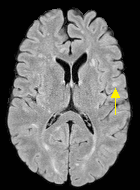

Patch size is another important parameter of the network. In computer vision applications such as object detection, usually a whole 2D image is used as a feature. However, full 3D medical images can not typically be used because of memory limitations. Fig. 4 shows examples of lesion memberships obtained with different sized 2D patches. As the patch sizes increases, the false positives that are mostly observed in the cortex tend to decrease. Fig. 5 shows a plot of Dice and LFPR with various patch sizes, ordered from left to right according to their increasing size. Note that smaller patches ( to ) produced significantly lower Dice and higher LFPR compared to other patches (), as seen from the memberships in Fig. 4. Also some of the highest Dice and lowest LFPR were observed for patches with large in-plane size, i.e., , , and . It was observed in Fig. 5 that there is no significant difference between Dice coefficients for , , or , but LFPR of both and are significantly lower than that of (). We chose as the optimal patch size. Other choices of smaller and patches (not shown) yielded worse results. Note that although training was performed with different patch sizes, the memberships were generated slice by slice, as the trained model consisted only of convolutions and did not need any information about patch sizes.